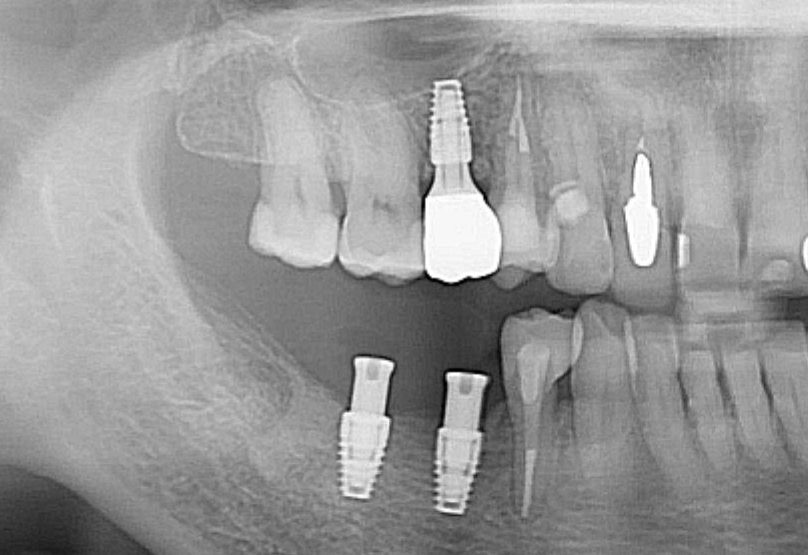

50代の女性の方のケースをご紹介します。

右側上下の奥歯の治療を行っています。

インプラントやマイクロスコープ下での根管治療、補綴治療(被せ物)を行いました。

以前治療した歯の状態が悪くなり、当院を調べて来院されました。

インプラントを行った部位の歯は、神経の処置がしてあり、痛みはありませんでしが、2次虫歯が酷く、また骨(歯槽骨)が破壊されており、残念ながら抜歯を行いました。

骨の状態も悪く、そのままではインプラントが埋入できなかったので、GBR(骨を造る処置)を行って埋入しています。

インプラントの手前の歯は、根管治療を行いセラミックの被せ物をしました。

奥の歯2本は、それぞれ2次虫歯でしたが、神経は感染していなかったので、健康なエナメル質は温存して、セラミックとジルコニアで治療を行いました。

まだ下の歯の治療(今後、型どりをして、インプラントの上部構造を製作予定)がありますが、少しずつ綺麗になっていく自分の歯について、うれしそうに話している姿が印象的でした。